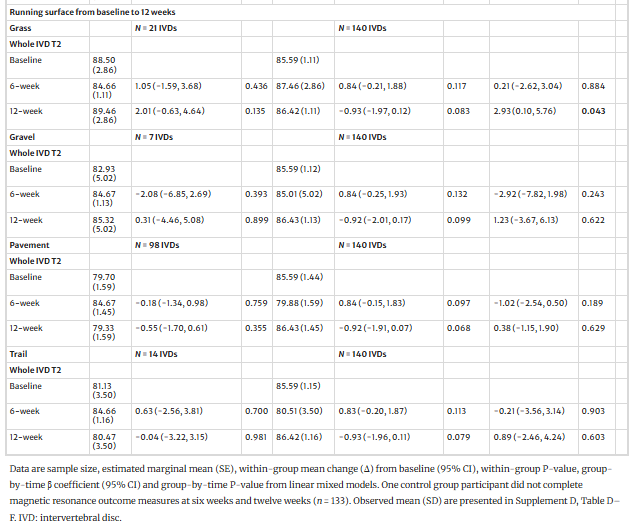

- Факторы вмешательства: Кумулятивный объем бега, средняя скорость бега и доминирующая поверхность для бега (трава, гравий, тротуар или тропа) оценивались с помощью бесплатного приложения Runkeeper. Совокупный объем бега и средняя скорость бега были распределены по квартилям IVD для анализа от исходного уровня до 12 недель. Все модераторы вмешательства сравнивались с контрольной выборкой.

Средняя скорость бега от 10,5 до 11,7 км/ч положительно повлияла на межгрупповой показатель IVD T2 через 12 недель. В то время как средняя скорость бега от 4,4 до 8,5 км/ч отрицательно влияла на IVD T2 только через шесть недель. Бег по траве положительно повлиял на межгрупповой показатель IVD T2 через 12 недель.

Вмешательство в виде бега с ходьбой было разработано как консервативное, что привело к широкому разбросу средних скоростей бега (от 4,4 до 11,7 км/ч) и суммарных объемов бега (от 1,8 до 109,8 км). Хотя это дало возможность провести анализ по подгруппам, он отражает высокую вариабельность фактической "дозы" бега.

Скорость бега и поверхность имеют значение: Наилучшие результаты были достигнуты при скорости бега 10,5-11,7 км/ч. Бег по травяной поверхности также оказывал положительный эффект на IVD. Индекс массы тела не оказал никакого модераторского влияния.